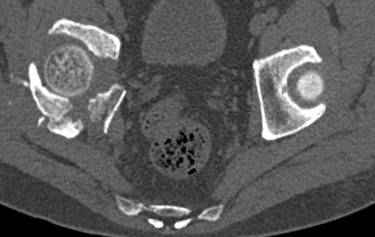

высылаю дополнительно сканы.

итак, второй вариант: высокий двухколонный с вовлечением КПС... Ни одно из основных повреждений не репонировано, кроме задней стенки. Скорее всего попытка реконструкции вертлуги сейчас будет очень травматичной и не очень эфективной, т.е. вероятный риск более значим, чем ожидаемая польза... Лучше подождать, и потом сразу эндопротез